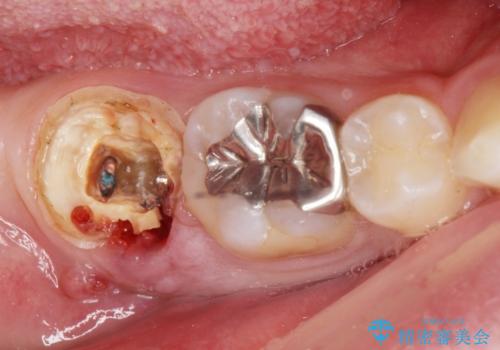

- 銀歯を白くしたいとのことで来院。

右下の被せ物を外し虫歯を除去したところ虫歯が深く保存が難しい状態だったので抜歯を行いました。

手前の銀の詰め物のところは除去して拡大鏡下で虫歯を取り除き、ジルコニアクラウンで治療を行いました。